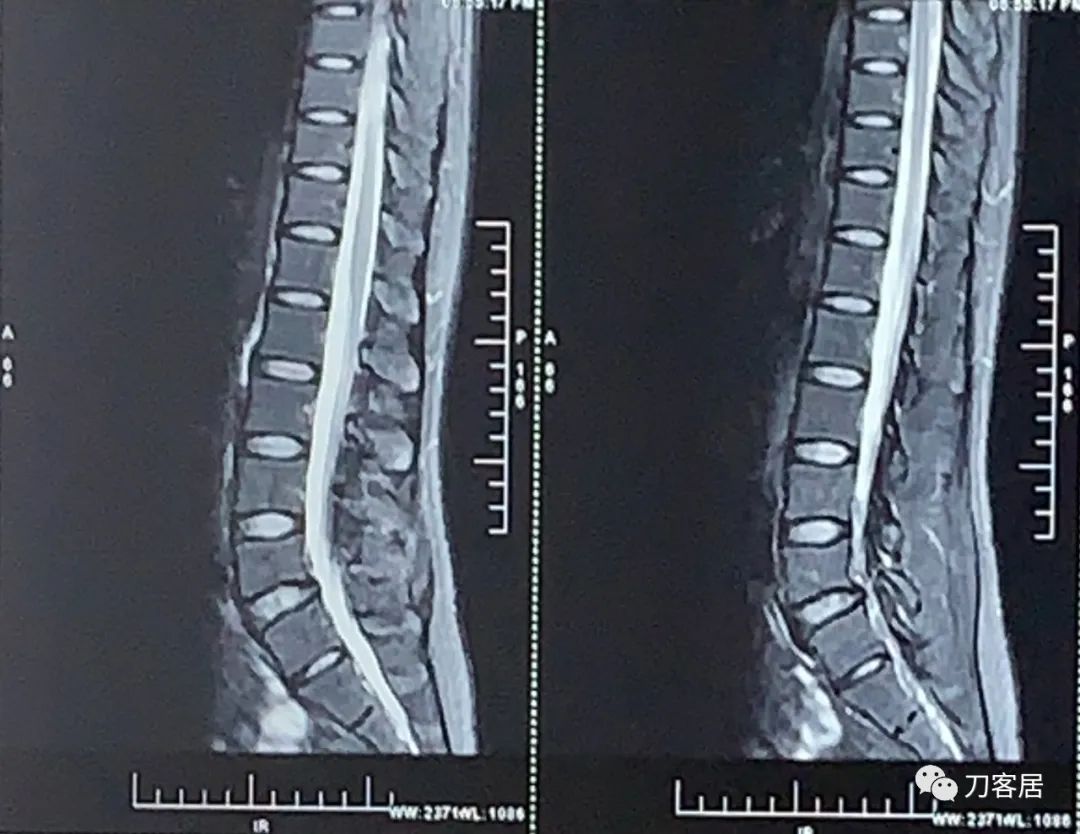

腰椎MRI提示未见严重的椎间盘突出及椎管狭窄。

图1. 20211122西安红会医院腰椎MRI1

图2. 20211122西安红会医院腰椎MRI2